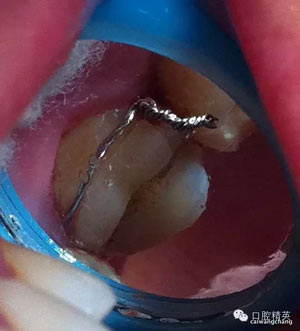

上圖可見該患者的牙斜向裂開,同時(shí)沒(méi)有做完善的根管治療

先給與根管充填(前提是無(wú)根管劈裂),牙膠截?cái)嘤诟芸?/span>

頰部預(yù)備溝槽,準(zhǔn)備結(jié)扎絲復(fù)位,現(xiàn)已改為成型夾或血管鉗鉗夾復(fù)位